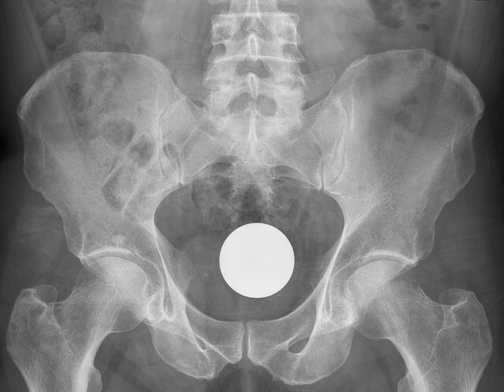

NASCONDEVANO 167 OVULI DI HASHISH NELL'INTESTINO: TRE ARRESTI. Tre giovani teramani, di età tra i 20 ed i 27 anni, sono finiti in manette ieri pomeriggio con l'accusa di traffico internazionale di sostanze stupefacenti. Il blitz anti-droga è scatato dopo che alla Questura di Teramo era giunta una "soffiata" circa il possibile arrivo in città di una partita i droga. Così sono partite le indagini che si sono concentrate da subito sui tre. Quando però una pattuglia della Questura è andata a bussare alla porta dell'abitazione i tre si sono subito innervositi ma in casa non c'era nulla. Gli agenti erano sicuri della notizia di reato così si è deciso di portarli al "Mazzini" di Teramo per vedere se, per caso, avessero ingerito lo stupefacente allo scopo di evitare l'arresto. E così è stato. La radiografia dell'ospedale ha da subito evidenziato la presenza di ovuli nell'intestino dei ragazzi. Sottoposti a specifico trattamento medico, in due giorni, hanno espulslo ben 167 ovuli di droga per un totale di 1 Kg e 240 grammi di hashish. Secondo i medici del nosocomio teramano hanno rischiato anche la morte perchè i contenitori, benchè termosaldati, potevano aprirsi ed intossicare gli intestini dei giovani fino a procurare uno stato di coma. Adesso le indagini sono indirizzate a scoprire il fornitore dello stupefacente che, da quanto si è saputo, è straniero. Il gruppetto, infatti, veniva da un viaggio all'estero e la droga era stata ingoiata proprio per evitare la polizia di frontiera.